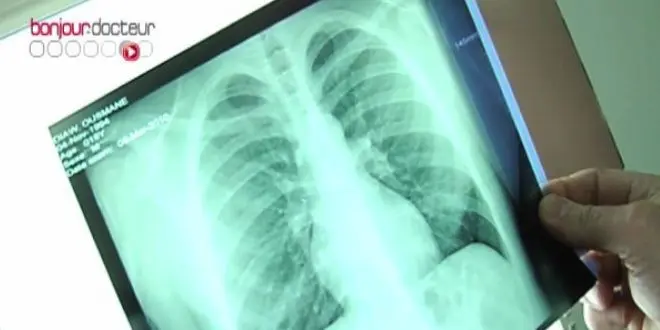

Un cas de tuberculose a été diagnostiqué ces derniers jours chez un élève d'un lycée de Jarny (Meurthe-et-Moselle), conduisant les autorités à organiser le 12 novembre un dépistage pour éviter toute contagion, selon une déclaration à la presse de l'Académie de Nancy-Metz.

La tuberculose affecterait environ 5.000 personnes par an en France, un chiffre en recul quasi constant depuis 20 ans, selon l'Institut national de veille sanitaire (InVS). La Guyane, Mayotte et l'Ile-de-France sont les régions les plus concernées.

Seules les formes respiratoires de la maladie sont contagieuses : le bacille de Koch se transmet par voie aérienne, par l'intermédiaire des sécrétions émises par une personne atteinte de tuberculose contagieuse, notamment en toussant, en crachant ou en éternuant.